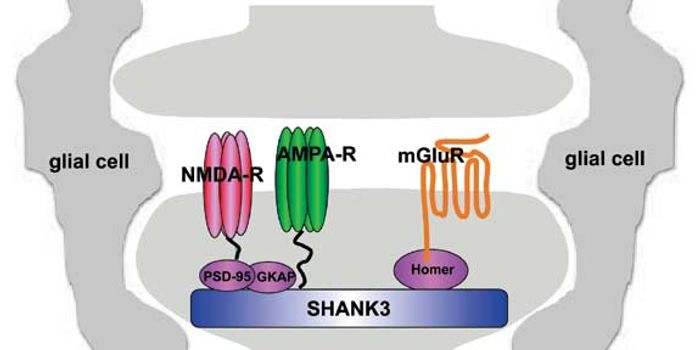

JUN 15, 2016Cell & Molecular BiologyAutism spectrum disorders (ASDs) is a group of developmental disabilities usually considered to be due to dysfunction in ...

MAY 16, 2016CardiologyWhen researchers examined human postmortem brain tissue—some from typical brains and others from those with an aut ...